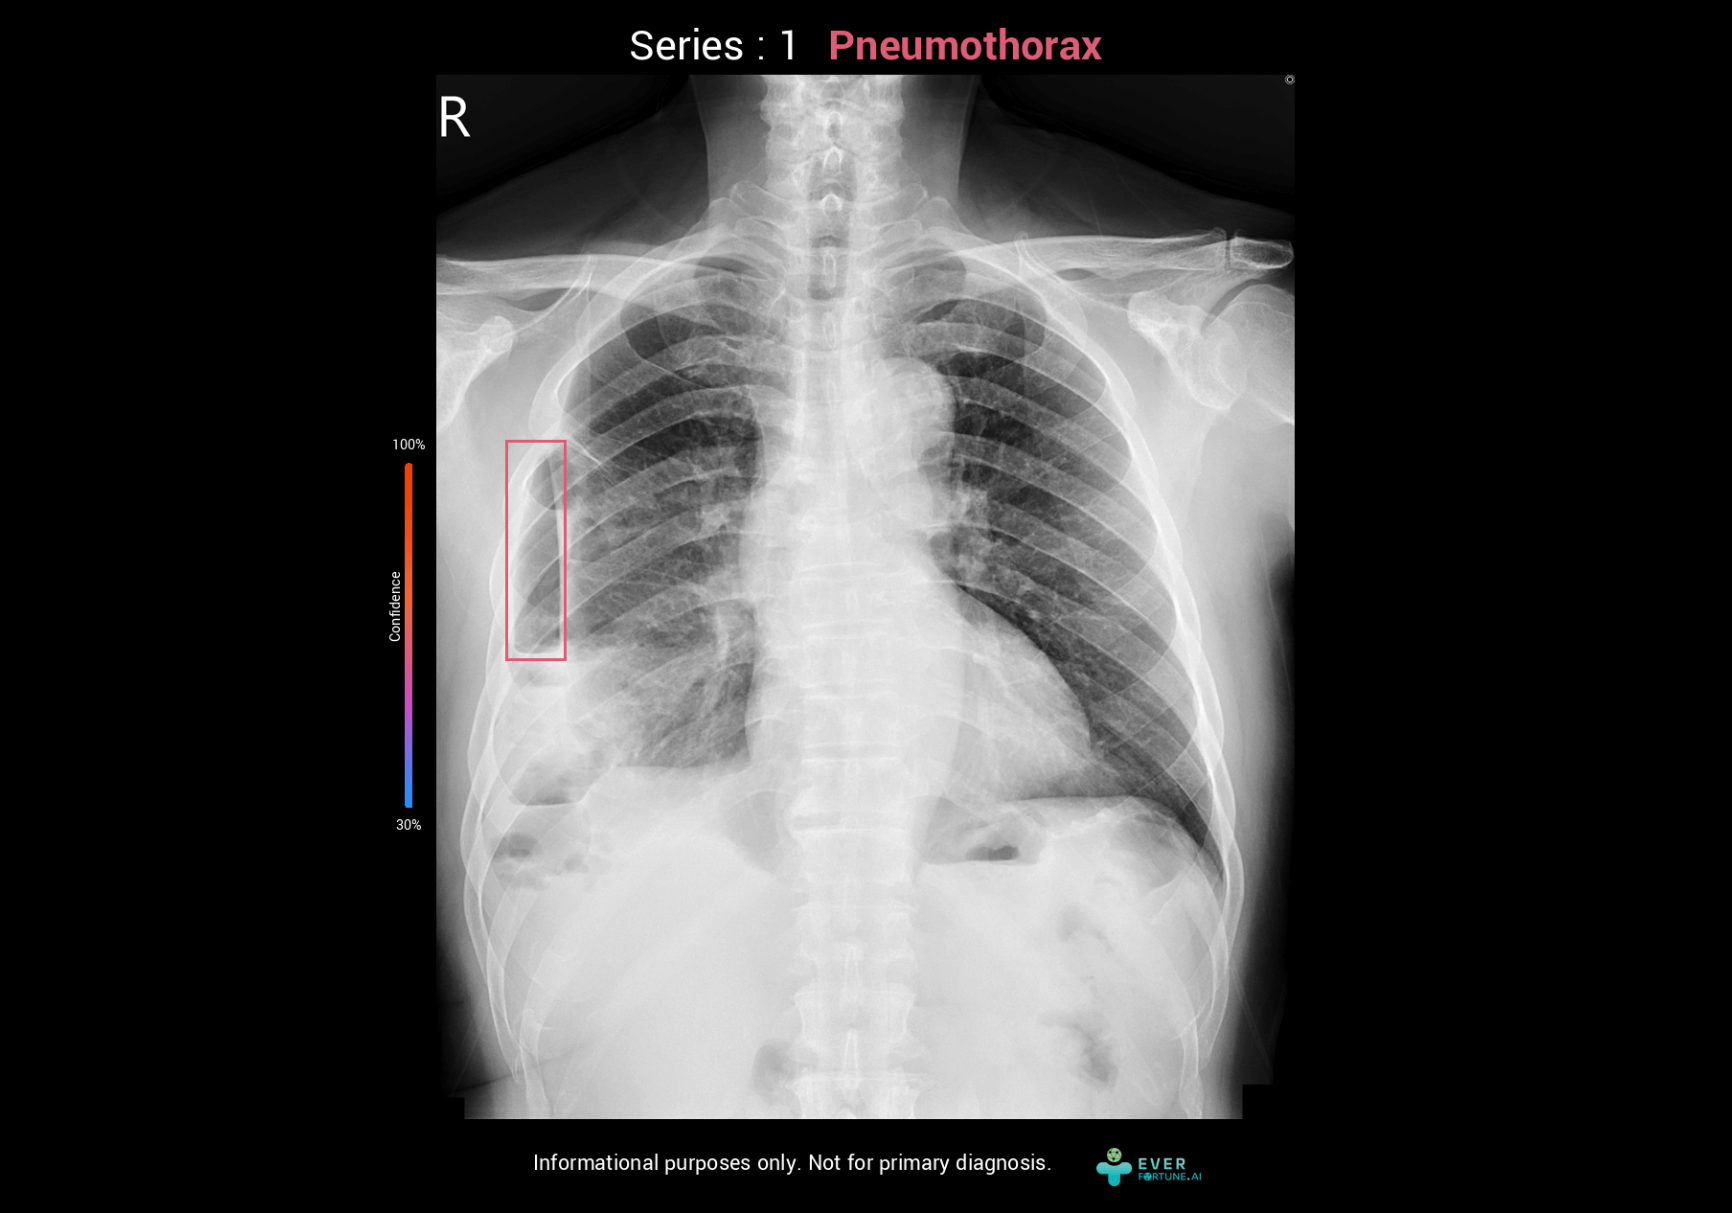

Our AI assistant for chest X-ray interpretation simultaneously assesses pneumothorax, pleural effusion, cardiothoracic ratio, and endotracheal tube depth. It provides key images seamlessly integrated with PACS for fast, highly accurate analysis results.

Identify 15 abnormal finding in chest X-ray images with heart, lungs and bones. The system as a pre-read assistance enable a quick interpretation and faster decisions